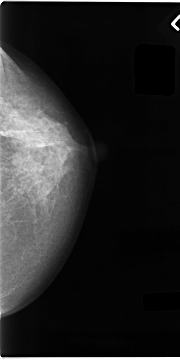

C_0061_1.RIGHT_CC

RIGHT_CC LINES 4704 PIXELS_PER_LINE 2664 BITS_PER_PIXEL 12 RESOLUTION 50 OVERLAY

FILE: C_0061_1.RIGHT_CC.OVERLAY

TOTAL_ABNORMALITIES 1

ABNORMALITY 1

LESION_TYPE MASS SHAPE IRREGULAR MARGINS SPICULATED

ASSESSMENT 5

SUBTLETY 5

PATHOLOGY MALIGNANT

TOTAL_OUTLINES 1

BOUNDARY